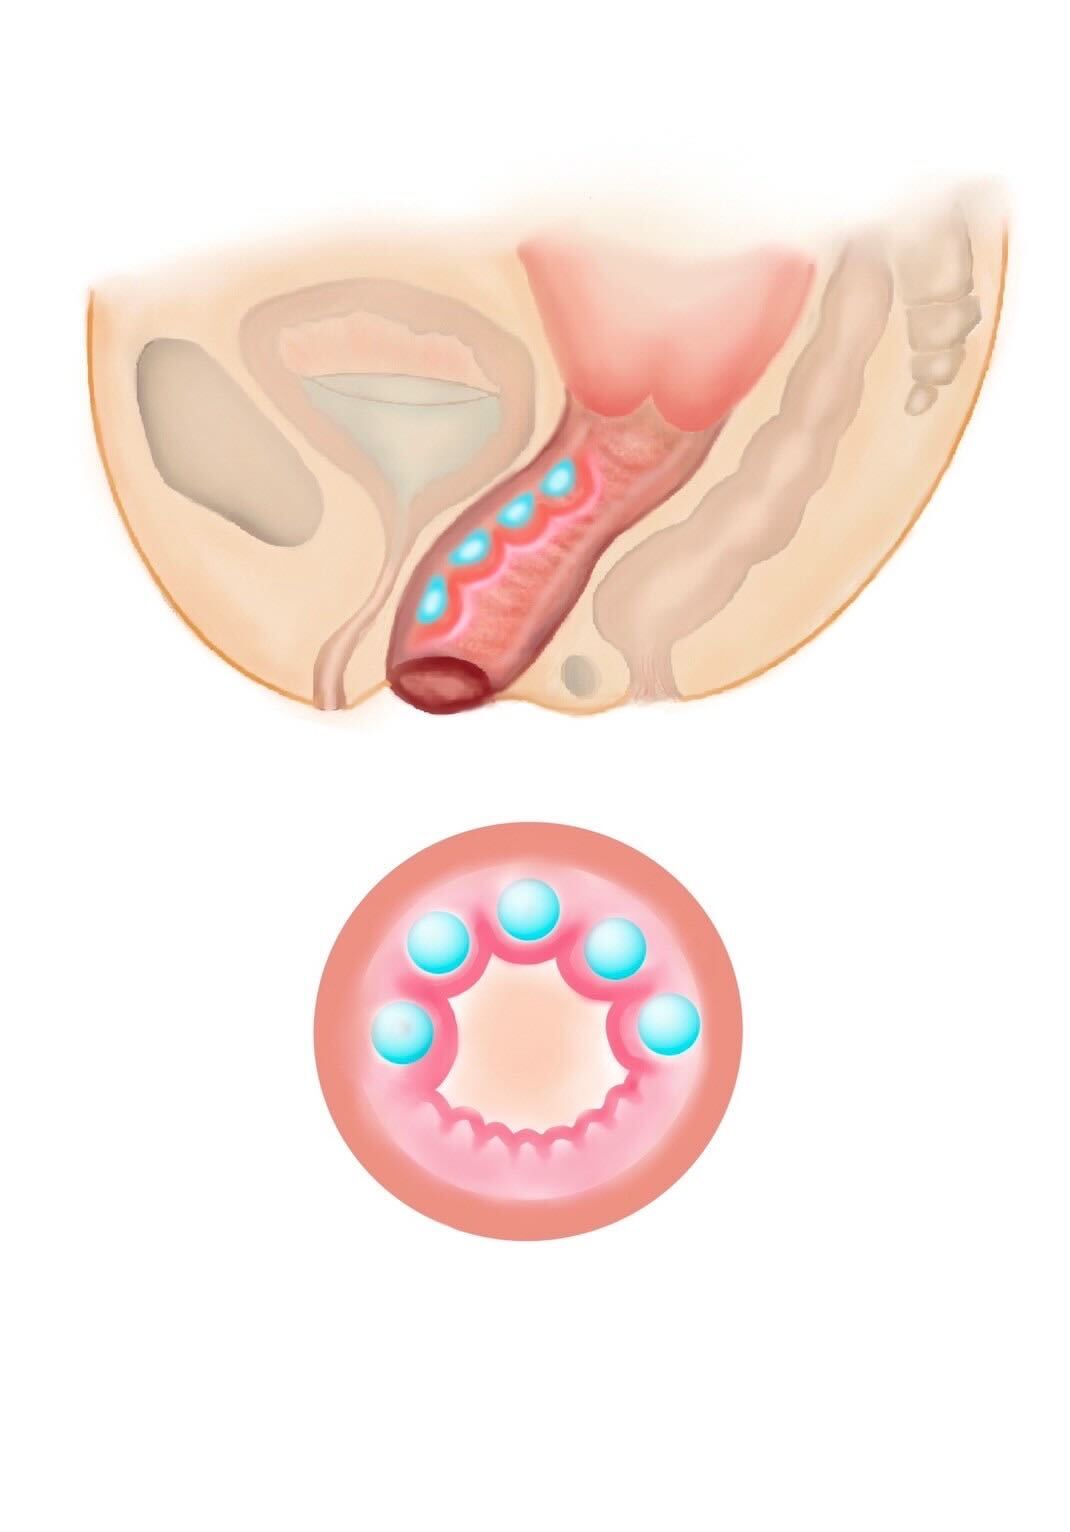

切らない膣縮小術/膣タイトニングスレッド

切らない膣縮小術は溶ける糸で数カ所縫縮することで癒着を促し、膣の粘膜部分を引き締める治療です。

切らない膣縮小術+膣内360度ヒアルロン酸注入(20ccまで)

膣を切らずにヒアルロン酸を膣内に注入し、膣入口の中を溶ける糸で縫い縮め、腟のゆるみを改善する施術です。糸は半年から1年で溶けていきますが、中で癒着するため効果が持続します。広がっていた膣が引き締まることにより入浴後のお湯漏れや空気漏れを改善する治療です。